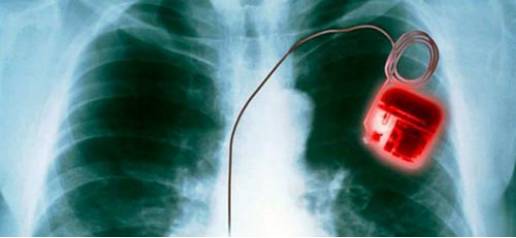

当前,物联网的安全形势非常严峻。许多智能设备,都变成了病毒滋生的场所。比如智能水壶,它可能被用来侵犯个人隐私;儿童的智能玩具也可能面临攻击;甚至父母的心脏起搏器也可能被黑客操纵。这些现象充分显示出,物联网的安全问题已经对人们的日常生活和企业的运作产生了重大影响。